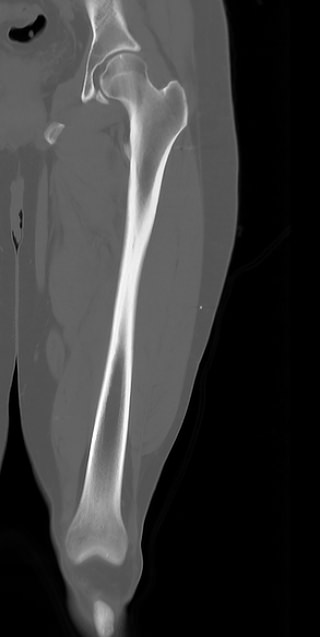

Бедренная кость является наиболее крупной трубчатой костью скелета человека и выполняет основную опорную функцию, обеспечивая прямохождение человека. Головка бедренной кости соединяется с вертлужной впадиной костей таза, образуя тазобедренный сустав, обеспечивающий движения нижней конечности.

КТ предусматривает использование рентгеновского излучения, которое хорошо поглощается костной тканью. В результате сканирования и последующей цифровой обработки полученных данных получаются подробные снимки в различных плоскостях, а также трехмерные изображения бедренной кости и тазобедренных суставов, которые можно увеличить и повернуть в разные стороны.

Снимки высокого разрешения позволяют выявить минимальные изменения в костных структурах и окружающих тканях. Мультиспиральная КТ может применяться в экстренных ситуациях для диагностики травматических повреждений бедренной кости и тазобедренных суставов, в частности, при переломах шейки бедра. Кроме того, исследование незаменимо при планировании оперативного вмешательства, а также в послеоперационном периоде для оценки успешности проведенной операции и для отслеживания процесса восстановления.

КТ бедренной кости помогает выявить воспалительные изменения, очаги деструкции костной ткани, доброкачественные и злокачественные новообразования. При подозрении на опухолевый процесс дополнительно применяется контрастное усиление. Для этого пациенту внутривенно вводится контрастный препарат на основе йода, который в большей степени, чем окружающие ткани, поглощает рентгеновские лучи. Поэтому при попадании в опухолевые очаги он обеспечивает их яркую визуализацию на снимках КТ. Методика контрастирования помогает обнаружить опухоли минимальных размеров, определить точные границы опухолевого очага, степень его прорастания в окружающие ткани, эта информация необходима врачу для назначения эффективной тактики лечения.